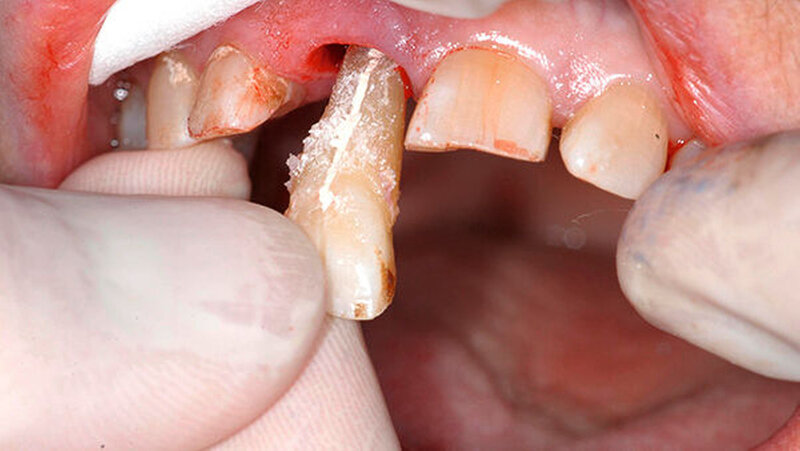

Bei der Vorstellung in der Poliklinik zeigte sich klinisch eine Schmelzfraktur auf der bukkalen Fläche des Zahns 11 (Abbildung 1). Die Messung der Taschensondierungstiefe (TST) ergab an dieser Stelle lokal begrenzt einen Wert von 7 mm (Abbildung 2). An allen übrigen Messpunkten lag eine physiologische TST von 3 mm vor.

Während die palatinale Fläche unbeschädigt war, zeigte die bukkale Fläche eine vertikale Frakturlinie (Abbildung 3), die mit einem feinen diamantierten Schleifkörper erweitert wurde (Abbildung 4). Zusätzlich erfolgte die Entfernung des retrograden Wurzelkanalfüllmaterials. Beide Defekte wurden mit Biodentine (Septodont, Niederkassel) aufgefüllt (Abbildung 5).